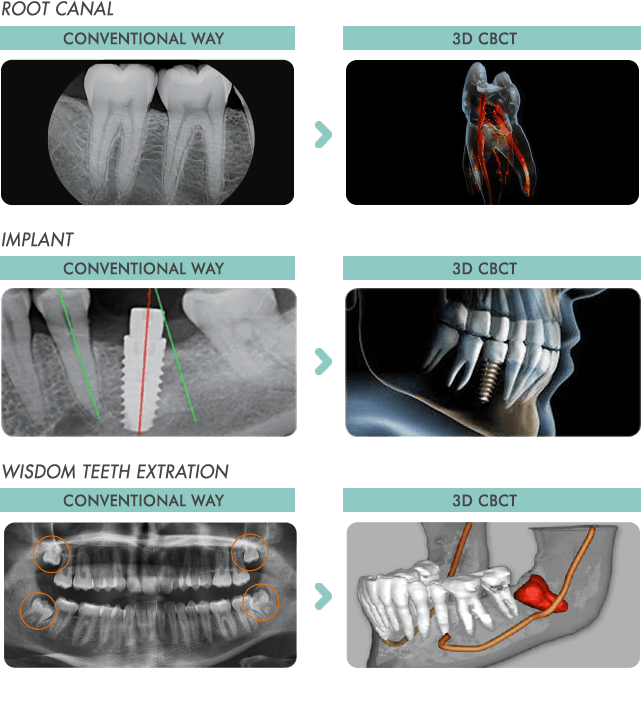

3D dental imaging is well on its way to become the new standard of dental care. This incredible technological advancement allows dentists to see your mouth in a way never previously possible with X-ray or medical CT scan technology. 3D dental imaging allows them to see your teeth and skull, diagnose any problems and provide more effective treatment for you.

To better understand what 3D dental imaging is, what it has done for the dental industry and what it can do for you and your dental care, we’ll walk you through the incredible machine that makes it possible.